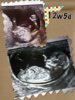

-serducho bije 165 u/min

-przezierność 1,4

-długość od głowy do pupci 5,5 cm

- nic więcej nie zbadała /kości nosowej itd/, bo dzidzia spała i nie chciała się ruszyć..

aha, wypatrzyłam wyrostek płciowy i wydaje mi się, ze... jest chłopczykowy hehe ginka oczywiście ani słowem nic nie mówiła o płci